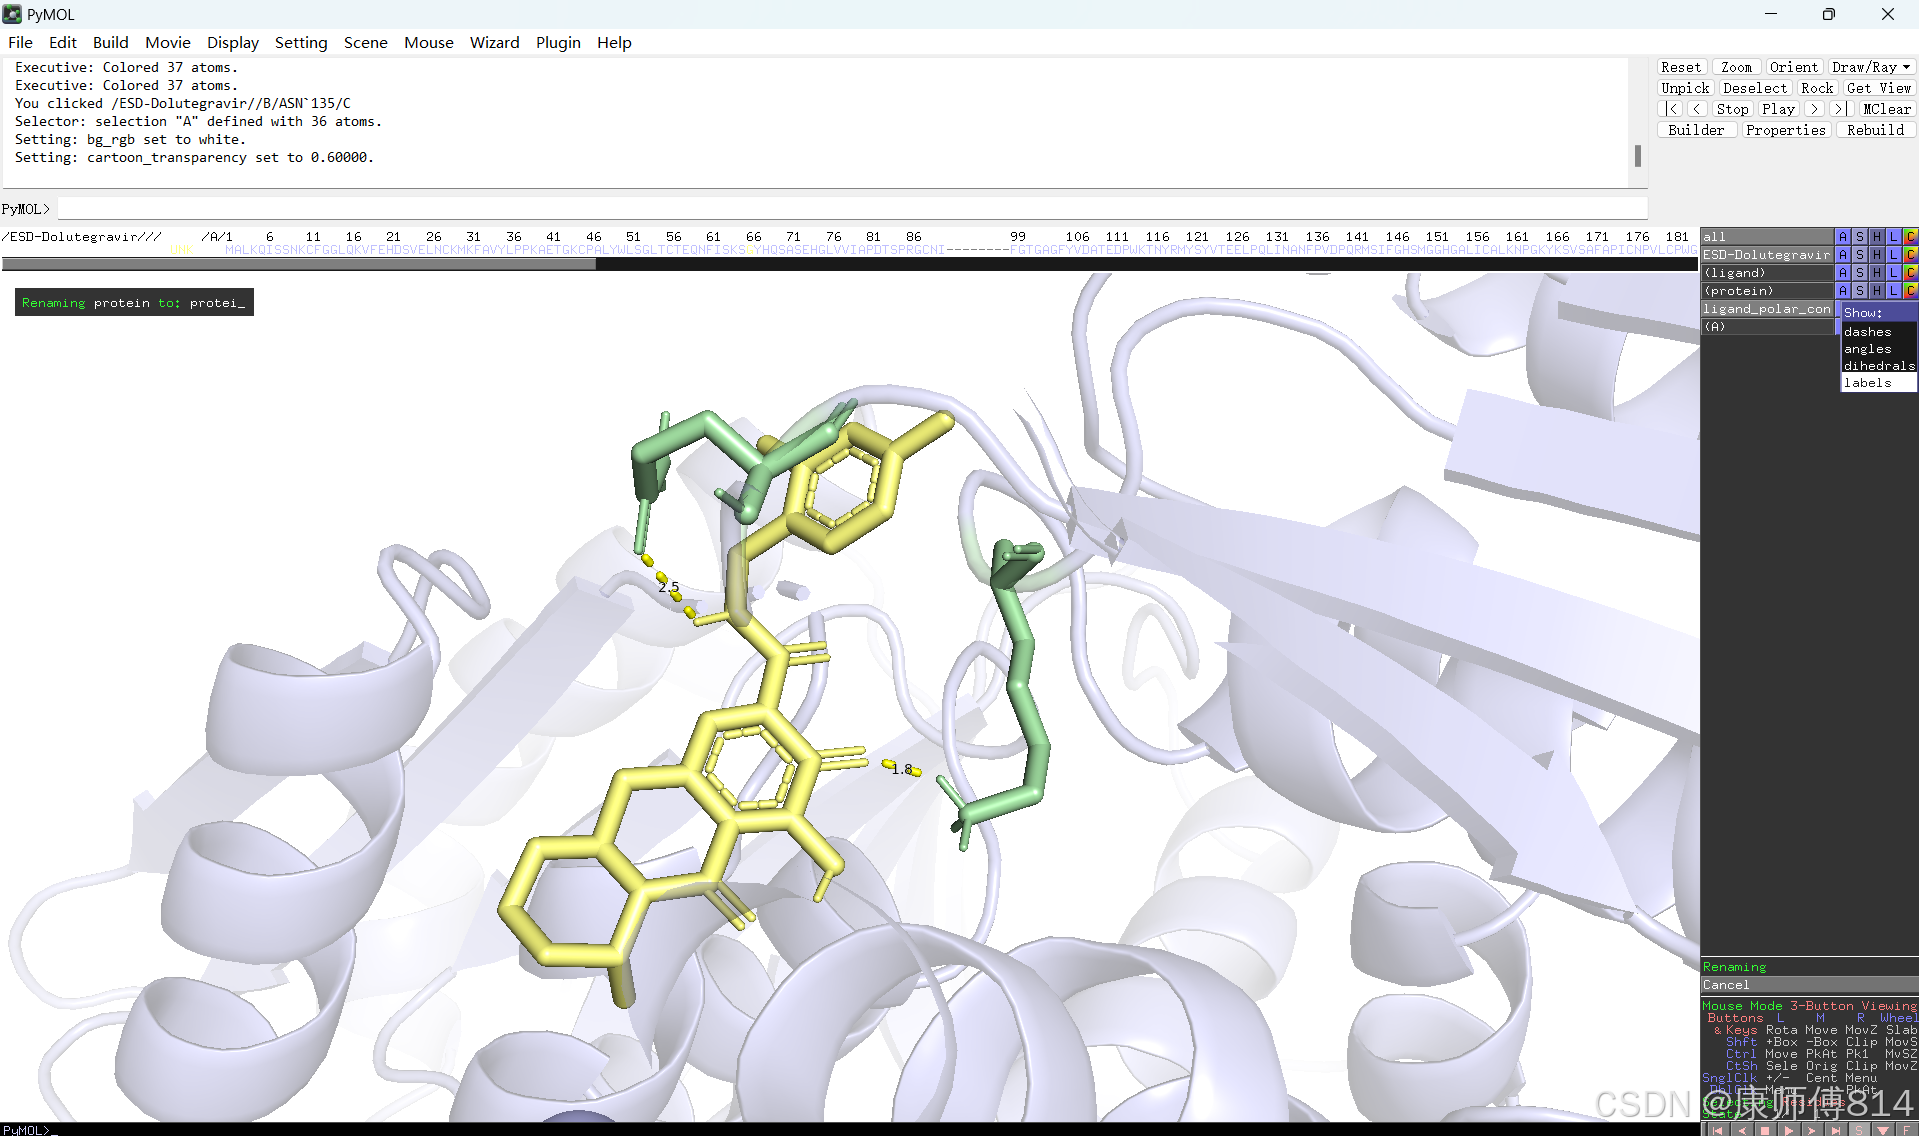

#此时展示分子对接的基本要素已经形成,后续可根据需要修改背景颜色、显示氨基酸残基名字以及氢键键能等等,这里不再赘述

#修改好后就可以导出了,点击右上角Draw,选择合适的格式导出即可

结果演示